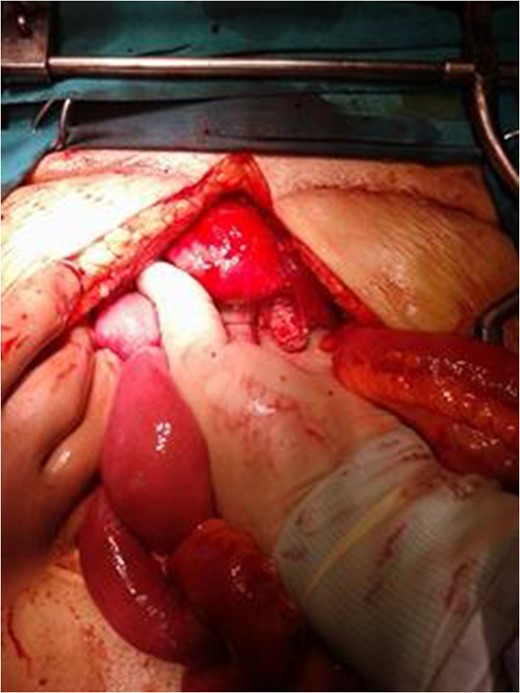

A reoperation was considered necessary some days later, which included total hysterectomy, bilateral salpingo-oophorectomy, omentectomy and appendectomy. No signs of ascites, carcinomatosis, or ovarian abmormalities were present (Figs 5 and 6). Histology of all excised specimens did not reveal any ovarian or other malignancies, leading, thus, to the conclusion that the initial mass was a primary solitary serous peritoneal tumor. The patient was advised to perform a 6-month follow-up control, due to reported poor prognosis of the condition.